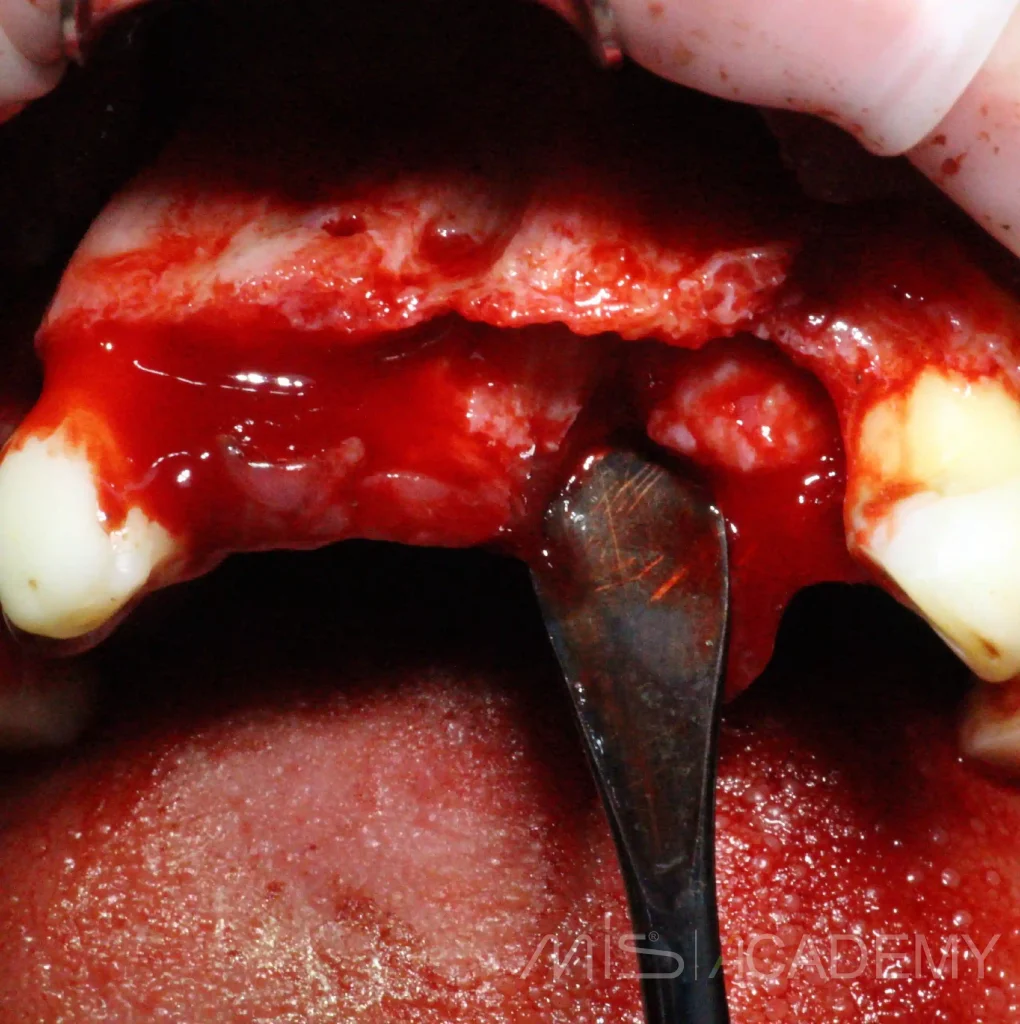

Клинический случай НКР верх фронт и последующие АО4 верх-низ.

На сегодняшний день возможно реализовал бы всё без НКР и возможно даже в FP1 (или аутоламинами, сократили бы сроки), но есть моменты по мягким тканям + вернусь ещё на устранение рецессии в области MU 24.